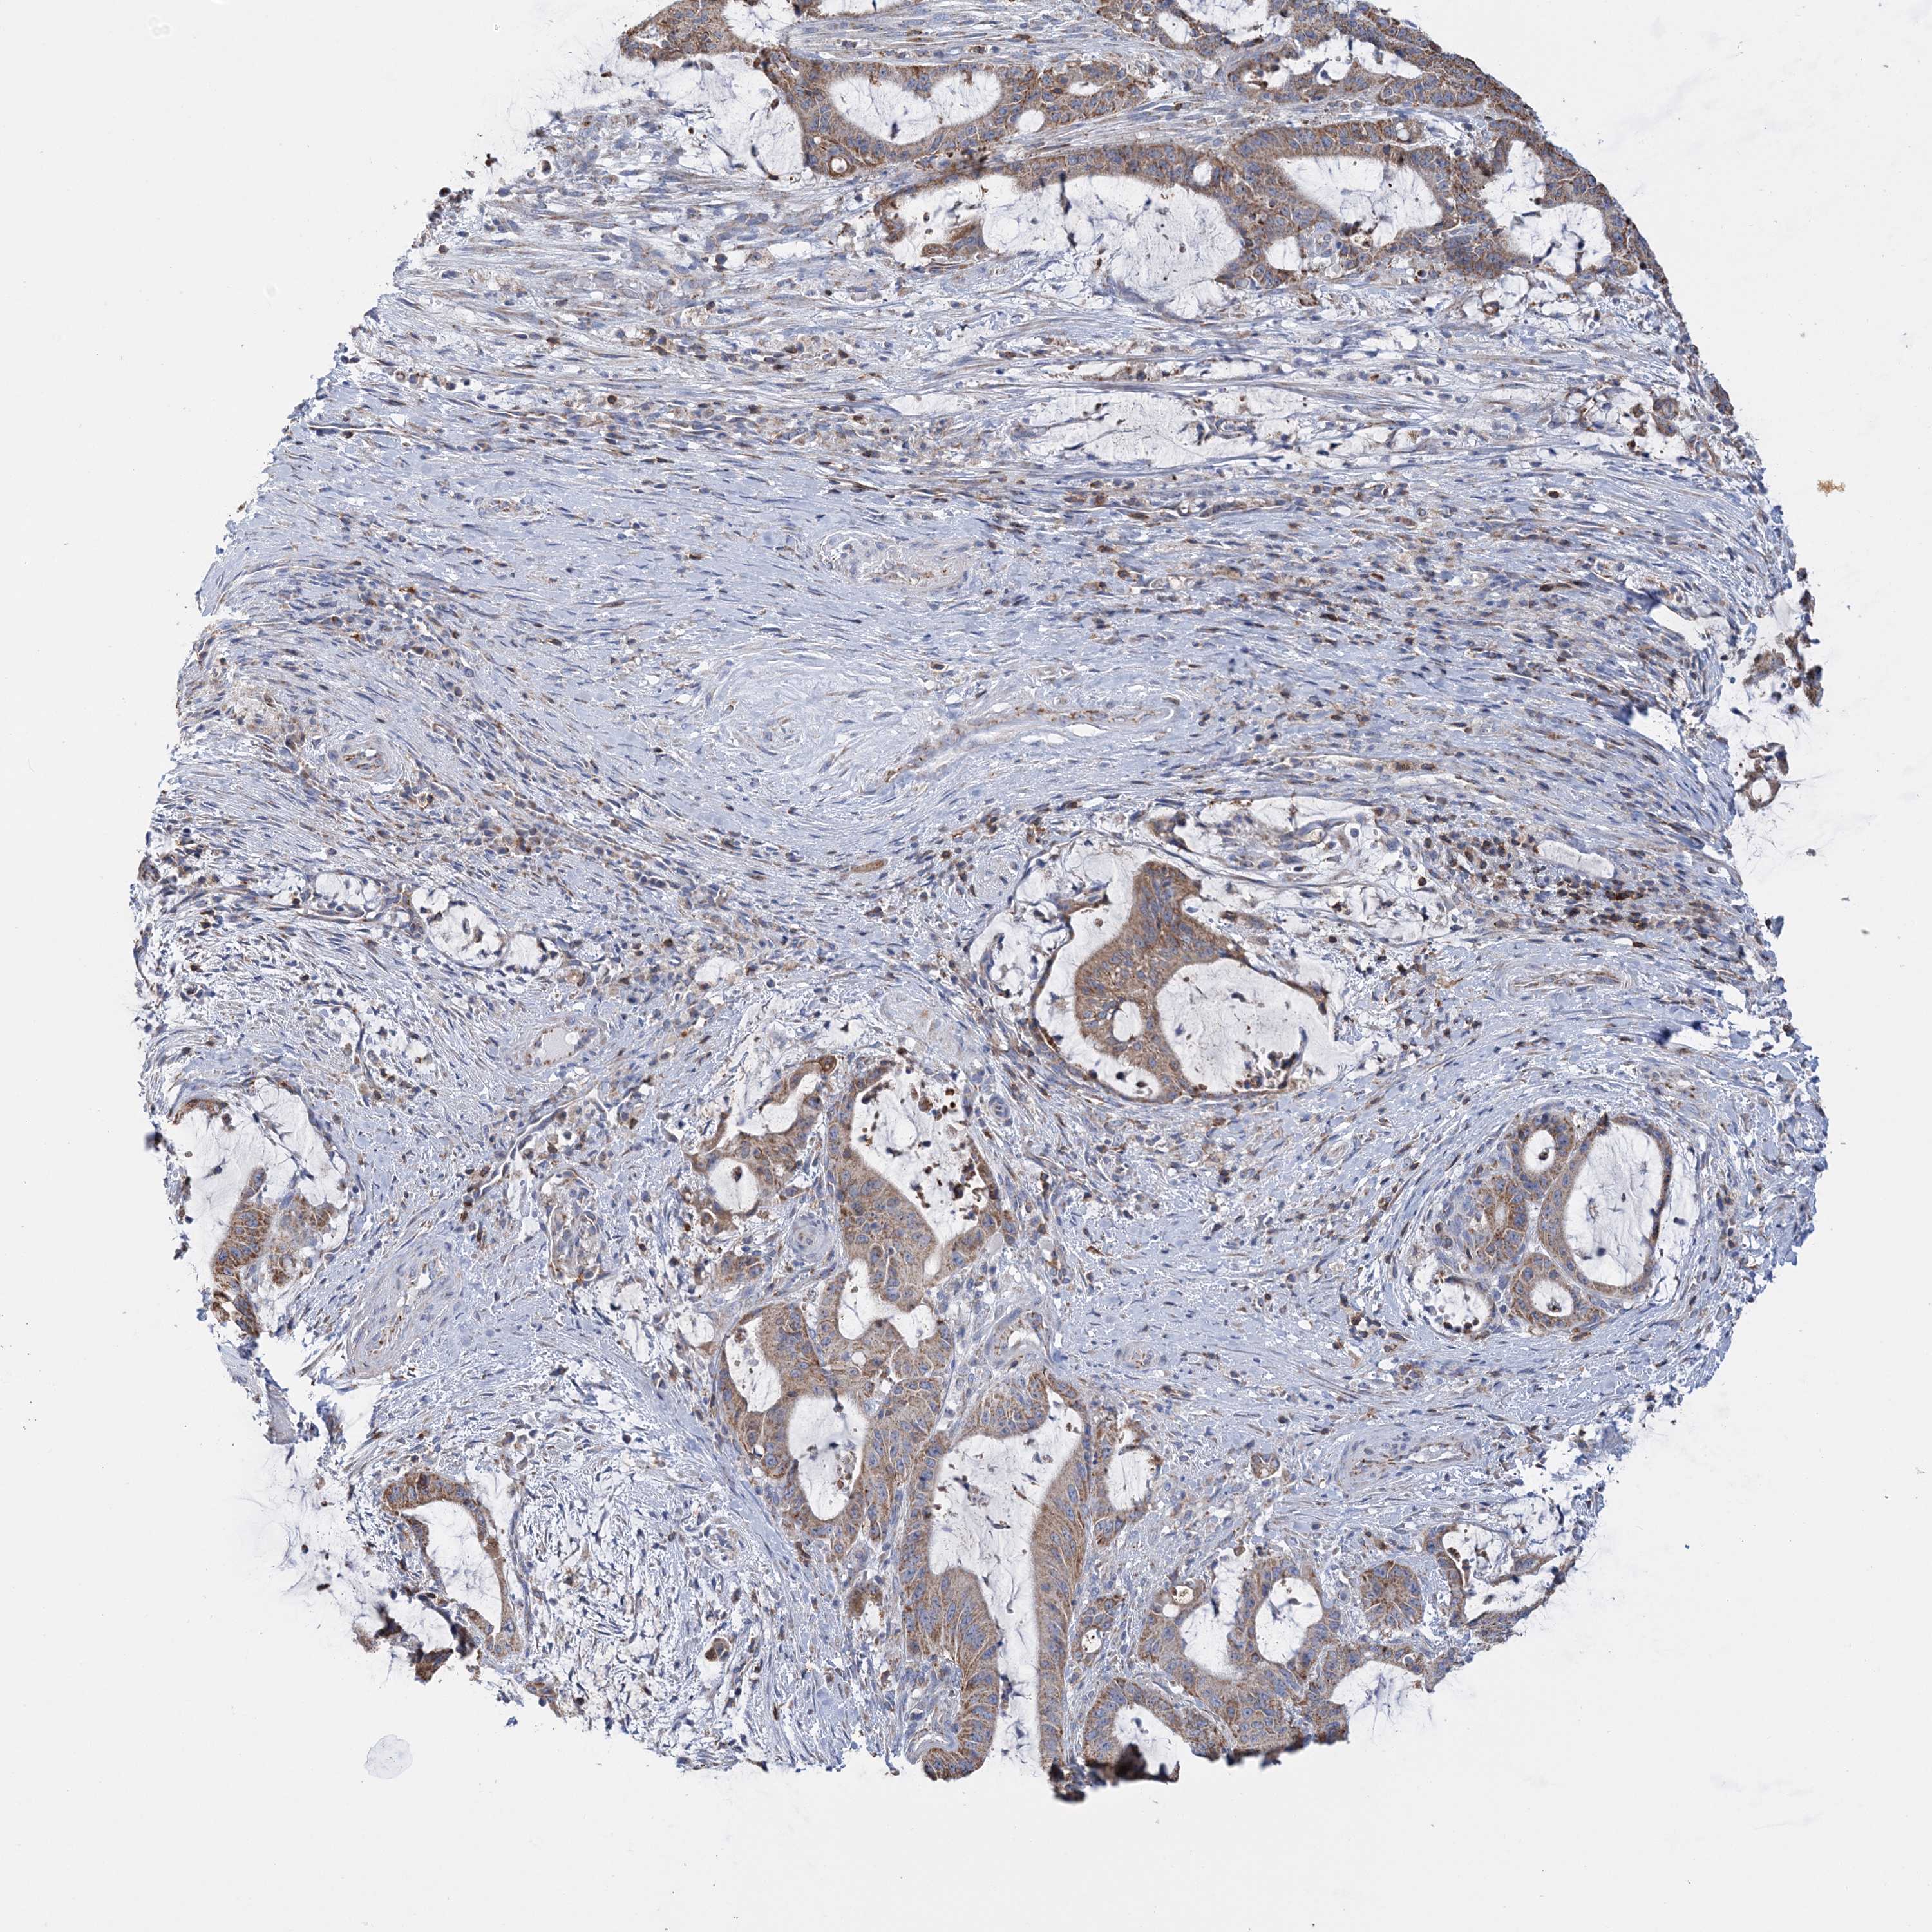

LIVER CANCER - Protein expressioni

A mouse-over function shows sample information and annotation data. Click on an image to view it in a full screen mode. Samples can be filtered based on level of antibody staining by selecting one or several of the following categories: high, medium, low and not detected. The assay and annotation is described here.

Note that samples used for immunohistochemistry by the Human Protein Atlas do not correspond to samples in the TCGA dataset.

Antibody stainingi

Antibody staining in the annotated cell types in the current human tissue is reported as not detected, low, medium, or high, based on conventional immunohistochemistry profiling in selected tissues. This score is based on the combination of the staining intensity and fraction of stained cells.

Each image is clickable and will lead to virtual microscopy that enables deeper exploration of all samples and also displays staining intensity scores, fraction scores and subcellular localization as well as patient and tissue information for each sample.

Antibody HPA036024

Staining

High

Medium

Low

Not detected

Intensity

Strong

Moderate

Weak

Negative

Quantity

>75%

75%-25%

<25%

None

Location

Nuclear

Cytoplasmic/membranous

Cytoplasmic/membranous,nuclear

Cholangiocarcinoma

Carcinoma, Hepatocellular, NOS